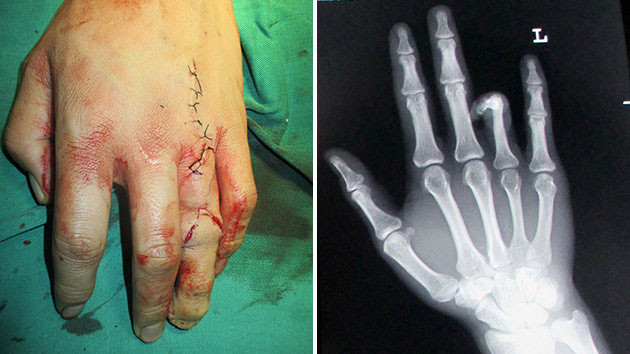

Ngón chân được ghép thay thế cho ngón áp úp của tay trái

Các bác sỹ phẫu thuật ở tỉnh Hồ Nam, Trung Quốc đã cố gắng tách ngón chân trỏ trái, dùng nó thay thế cho ngón áp úp bị mất của cậu.

Bác sỹ Lu, người thực hiện phẫu thuật cho biết: “Rất khó để nhận ra sự khác biệt nếu thoạt nhìn qua. Điểm khác biệt duy nhất đó là kích thước móng”.